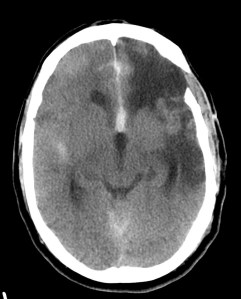

Paciente de 58 años que acude a urgencias con pérdida de conciencia y que, según un familiar, se quejaba de una cefalea «muy insoportable», de inicio súbito y que comenzó hace 20 minutos aproximadamente.

TA 175/100; FC 105; Sat 02 96%.

Se realiza TC de cráneo sin contraste, objetivándose:

Estamos ante una Hemorragia Subaracnoidea por rotura aneurismática.

Aunque la RM tiene mayor sensibilidad para el diagnóstico de sangrado, es la TC la prueba de primera línea debido a su mayor disponibilidad. Observaremos la característica imagen de hiperdensidad en las cisternas basales que corresponde a la sangre extravasada. La mayoría de las veces veremos el característico aumento de densidad alrededor del polígono de Willis (65%), que es donde ocurren la mayoría de las roturas de aneurismas, y también en la región de la cisura de Silvio (30%). Podemos ver también sangre en la fosa interpeduncular o asta occipital de los ventrículos laterales.